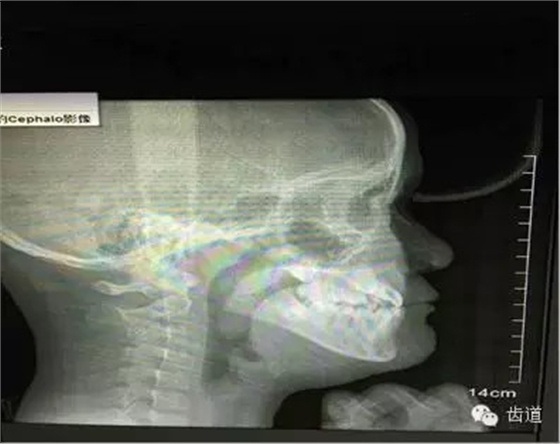

來源:齒道 源于“齒道-(牙合)學(xué)學(xué)習(xí)群”病案討論 文字編輯整理:周文翹 微信編輯:黃春梅 總編: 齒道—(牙合)學(xué)微信群里大咖云集,是廣大(牙合)學(xué)愛好者的相互學(xué)習(xí)、共同討論的理想平臺。(牙合)學(xué)并不神秘,群(牙合)學(xué)老師權(quán)花淑認(rèn)為:每一位臨床醫(yī)生每天都會面臨各種困惑和難題,作為初學(xué)者,只要我們堅持思考、善于溝通、勤于實(shí)踐,(牙合)學(xué)的神秘大門將會為我們敞開。下面,讓我們跟隨近日學(xué)習(xí)群里的部分病例,尋找(牙合)學(xué)的蛛絲馬跡。 圖1 權(quán)老師從(牙合)學(xué)的角度提出: 以上側(cè)片中應(yīng)關(guān)注舌的位置,由此會引發(fā)出更多需要關(guān)注的問題(如:舌的位置是否與氣道、牙弓狹窄、中線偏斜等有關(guān))。 病例二:(權(quán)老師會診病例圖2、圖3)患者,女,24歲。主訴:左側(cè)顳下頜關(guān)節(jié)區(qū)張口疼痛,打哈欠時疼痛更明顯。從以下CBCT截圖中,我們能讀出哪些信息? 圖2 圖3 多位醫(yī)生均發(fā)現(xiàn): 左7正鎖合,47根管治療,中線不齊,切端對刃,下前牙扭,下前牙牙根吸收等問題。同時也提出一些疑問:前伸(牙合)是否有異常,髁突是否對稱,關(guān)節(jié)盤的位置是否正常等。 權(quán)老師指出: 通過CT和臨床檢查,患者覆蓋和覆(牙合)不足;開口度尚可,開口型呈“Z”型軌跡;左側(cè)咬肌區(qū)有輕微壓痛,無明顯彈響和其他雜音;髁突疑似吸收,升支似乎變短。初步診斷正鎖合是引起同側(cè)TMJ疼痛的原因。雖然信息有限,但我們依然可以從中學(xué)習(xí)到東西,用(牙合)學(xué)的思維去驗證和排除我們的疑問和猜想。 權(quán)老師從(牙合)學(xué)的角度提出: 磨耗是一種慢性疾病,任何時候都是亡羊補(bǔ)牢。后牙單顆牙磨耗的情況是不存在的,只是個別牙會表現(xiàn)得更明顯。要從整個牙列甚至整個口頜系統(tǒng)去分析,還應(yīng)該權(quán)衡整體解決或保守治療。單顆牙修復(fù)可視為一種方法,但它是保守被動的治療方法。 以上病例,你是否用(牙合)學(xué)的眼光捕捉到一些蛛絲馬跡了?請繼續(xù)跟隨權(quán)老師學(xué)習(xí),讓我們一起漸入佳境! 貼心的權(quán)老師推薦(牙合)學(xué)初學(xué)者們把(牙合)學(xué)教材作為入門書,同時推薦了王美清老師、韓科老師、謝秋菲老師編寫的有關(guān)書籍。 合學(xué)的世界邀請您 中國醫(yī)學(xué)界,牙醫(yī)是個非常特別的群體! 自由執(zhí)業(yè)度最高的,是牙醫(yī)! 最有活力的,也是牙醫(yī)! 最愛學(xué)習(xí)的,還是牙醫(yī)! 每次研修,都好象畫圓。學(xué)得越多,圓的半徑越大。圓畫得越大,接觸的東西也越多…… 當(dāng)牙醫(yī)遇到合學(xué)時,一扇奇特的門打開了! 合學(xué),研究的是整個口頜系統(tǒng)的形態(tài)與功能,生理與病理,它不是玄學(xué),卻非常美妙。 學(xué)習(xí)合學(xué)開啟合學(xué)之門 優(yōu)秀牙醫(yī)必然的選擇